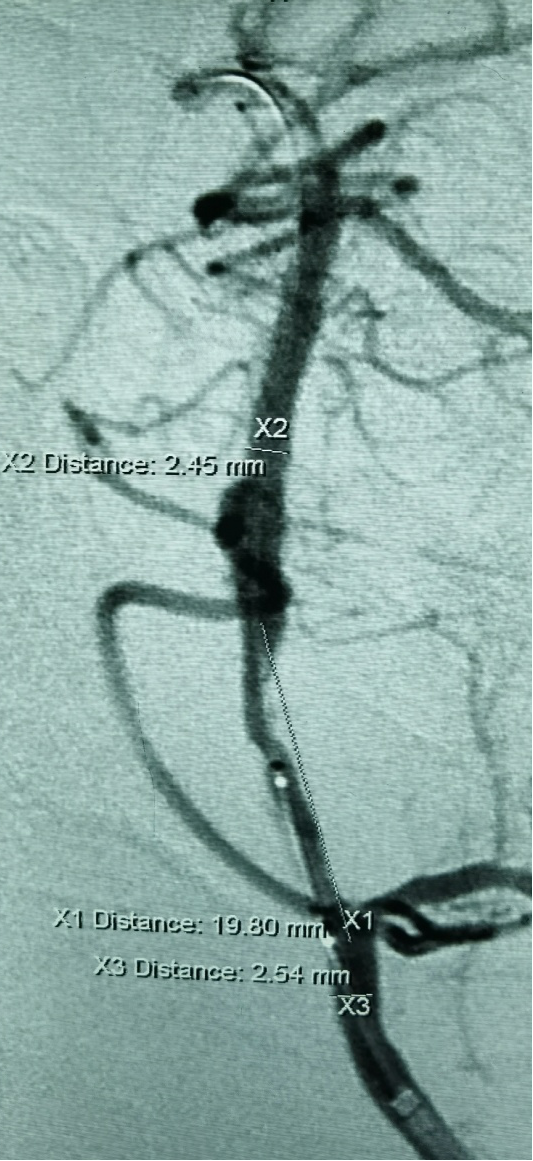

引入加奇SacSpeed® 2.0mm×12mm颅内球囊扩张。

扩张后造影,提示恢复正向血流,残余狭窄50%左右。

换用加奇SacSpeed® 2.5mm×12mm颅内球囊扩张。

扩张后造影提示,正向血流理想,闭塞节段成型理想。

选择Neuroform EZ 3.5X20mm支架植入,术后工作角度造影如下:

术中操作技巧:闭塞再通最关键的步骤就是导丝如何通过闭塞节段。一般选用微导管微导丝配合技术,增加微导丝的支撑力和操控性。术中要手感柔和,尽量尝试寻找最后的闭塞通道,找到原始的狭窄管腔通过。切记不可粗暴操作,避免进入夹层或扎破血管。球囊可以先选用小球囊预扩,再选用大球囊后扩,循序渐进。球囊直径达到原始管腔80%左右即可,不要求完美成型,避免造成扩张后损害血管或出血风险。该病人选用加奇SacSpeed® 2.0mm×12mm颅内球囊预扩,再选用加奇SacSpeed® 2.5mm×12mm颅内球囊后扩。